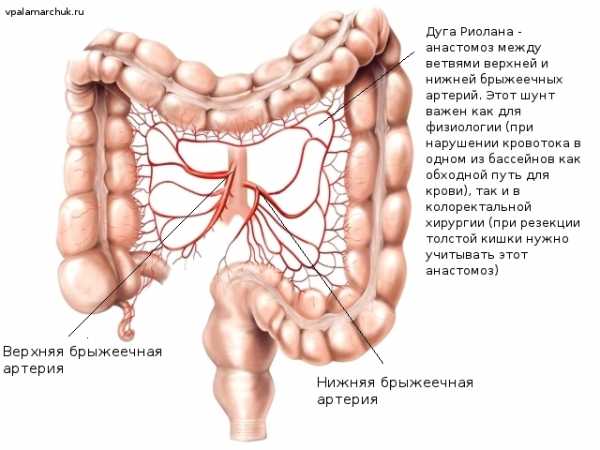

Кровообращение толстого кишечника

Приток крови осуществляется мощными сосудами, отходящими от аорты: верхней и нижней брыжеечной артерией. При попадании тромба (сформировавшегося, например, при мерцательной аритмии в предсердии сердца) в один из этих сосудов развивается очень тяжелое неотложное заболевание — мезентериотромбоз. Последствия очень часто фатальны. А вот с мелкими артериями, питающими кишку все намного лучше за счет многочисленных анастомозов. Как кружевные петли, они обеспечивают непрерывный кровоток при перистальтике и постоянном смещении кишечных петель. При массивном атеросклерозе же может развиваться заболевание — ишемический колит. Или «брюшная жаба»: по аналогии с болями за грудиной при ишемии сердечной мышцы — «грудной жабе». Между бассейнами верхней и нижней брыжеечных артерий в области селезеночного угла имеется анастомоз — дуга Риолана.

Весь венозный отток собирается в воротную вену и идет через «фильтр» — печень. Исключение — небольшая часть крови минует печень в прямой кишке, где есть т.н. портокавальные анастомозы. Кровь поступает «мимо» печени в нижнюю полую вену. Это может иметь значение при ректальном введении лекарственных средств.